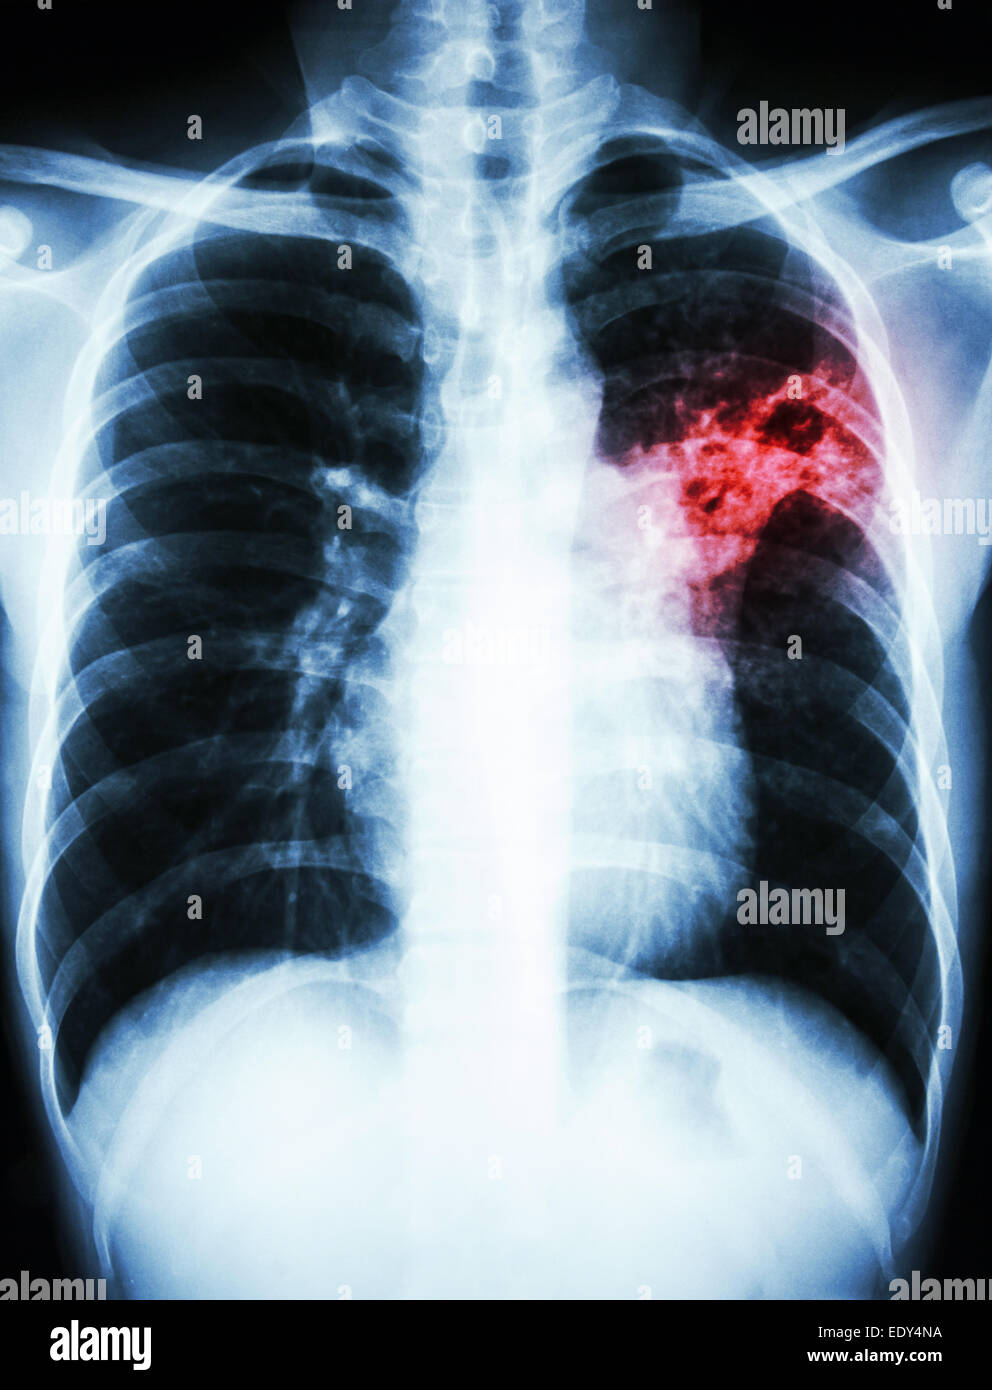

From www.alamy.com

Pulmonary Tuberculosis ( TB ) Chest xray show alveolar infiltration Do Chest X Rays Show Infection We can see infections and pneumonias. Pneumonia is an infection of the lung. A sputum culture can help determine whether the infection is bacterial or viral. There are no visible nodules, tumors or masses. These will appear most commonly as hazy or white areas in the lungs. Blood tests are used to confirm an infection and to try to identify. Do Chest X Rays Show Infection.